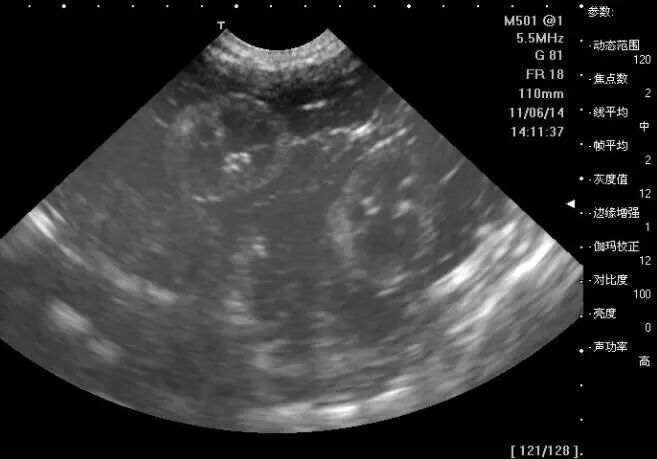

可是各项数据好像天书,什么BPF、FL啊,真的很头疼,这些到底是什么意思,反映了什么情况呢?宝妈们一起来看看吧:

BPF:双顶径,是指胎儿头部从左到右最长部分。

FL:股骨长,是指的是大腿的长度。

腹围:胎儿肚子一周的长度。

那么各项数据又都说明了什么问题呢?它们的正常范围值是多少呢?

项目

正常

异常

胎囊

只在怀孕早期见到。大小:孕1.5个月直径约2cm;2.5个月约5cm。位置:子宫宫底、前壁、后壁、上部、中部都属正常。形态:圆形、椭圆形、清晰。

位置:下部,且伴有腹痛或阴道流血,可能有流产的风险。形态:不规则形、模糊。

胎头

形态:轮廓完整,脑中线无移位和无脑积水。双顶径:孕5个月以后,基本与怀孕月份相符,例如孕7个月时双顶径约为7.0cm。孕8个月以后,平均每周增长约为0.2cm为正常。

形态:缺损、变形。

胎心

跳动:有、强。频率:120-160次/分钟。

跳动:无、弱。频率:过快、过慢、不规则。

胎动

有、强。

无、弱可能胎儿在睡眠,也可能为异常情况,要结合其它项目综合分析。

胎盘

厚度:2.5-5cm。钙化一项报告单:Ⅰ级为胎盘成熟的早期阶段,回声均匀,在怀30-32周可见到此种变化;Ⅱ级表示胎盘接近成熟;Ⅲ级提示胎盘已经成熟。越接近足月,胎盘越成熟,回声的不均匀。

太厚或太薄,都表示胎儿在宫内的生长情况有些异常,建议对胎儿进行进一步的检查,密切关注胎儿的生长状况。

股骨长度

与相应的怀孕月份的双顶径值差2-3cm左右,如双顶径为9.3cm,股骨长度应为7.3cm。

羊水

深度:3-7cm。

深度:超过7cm为羊水增多,少于3cm为羊水减少。

脊椎

脊柱连续为正常。

缺损为异常,可能脊柱有畸形。

脐带

正常情况下,脐带应漂浮在羊水中。

若在胎儿颈部见到脐带影像,可能为脐带绕颈